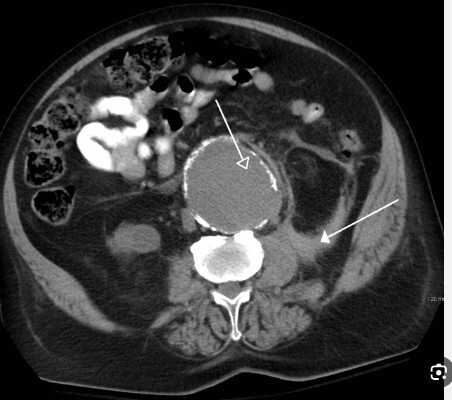

محققان روش تصویربرداری جدیدی را توسعه داده‌اند که با تشخیص دقیق حاشیه تومور‌های سرطان سینه قبل و هنگام جراحی به حفظ بافت سالم بیشتری کمک کند.

به گزارش خبرگزاری صدا و سیما ، پژوهشگران چینی در این تصویربرداری یک نشانگر زیستی را هدف قرار دادند که اغلب بر روی سطوح تومور بیش از حد بیان می‌شود و حاشیه‌های تومور را برای جراحی حفظ سینه (BCS) تشخیص می‌دهد.

یکی از روش‌های ارزیابی حین عمل که توجه را به خود جلب می‌کند، استفاده از تصویربرداری فلورسانس به دلیل سرعت تولید تصاویر در زمان واقعی، هزینه کم و سهولت استفاده است.